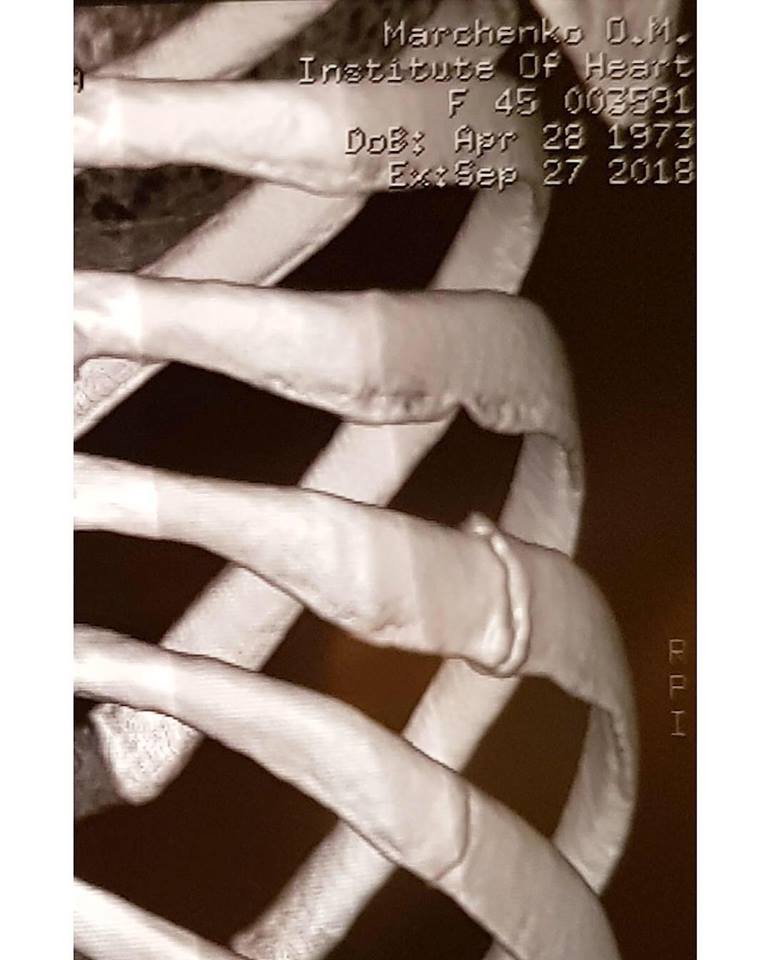

Телеведущая сообщила, что покидает проект после того, как выяснилось, что у нее сломаны два ребра. Травму она получила во время подготовки к прямым эфирам, на репетиции. Она ощутила острую боль, но подумала, что сильно потянула связки или мышцы. Первое время она принимала обезболивающее и продолжала репетировать и выступать на прямых эфирах. Но в итоге пришлось принять решение уйти из шоу, поскольку из-за усложняющейся программы врачи опасались рецедивов, ведь ткани в местах переломов еще достаточно слабые.

Она поблагодарила всех, кто за нее болел, семью и всех, кто делает шоу. И отдельно  своего партнера по танцам Дмитрия Чаплина. К посту Оксана Марченко приложила флюорографию ребер и медицинские справки, подтверждающие перелом двух ребер. А также фото с Дмитрием Чаплиным.